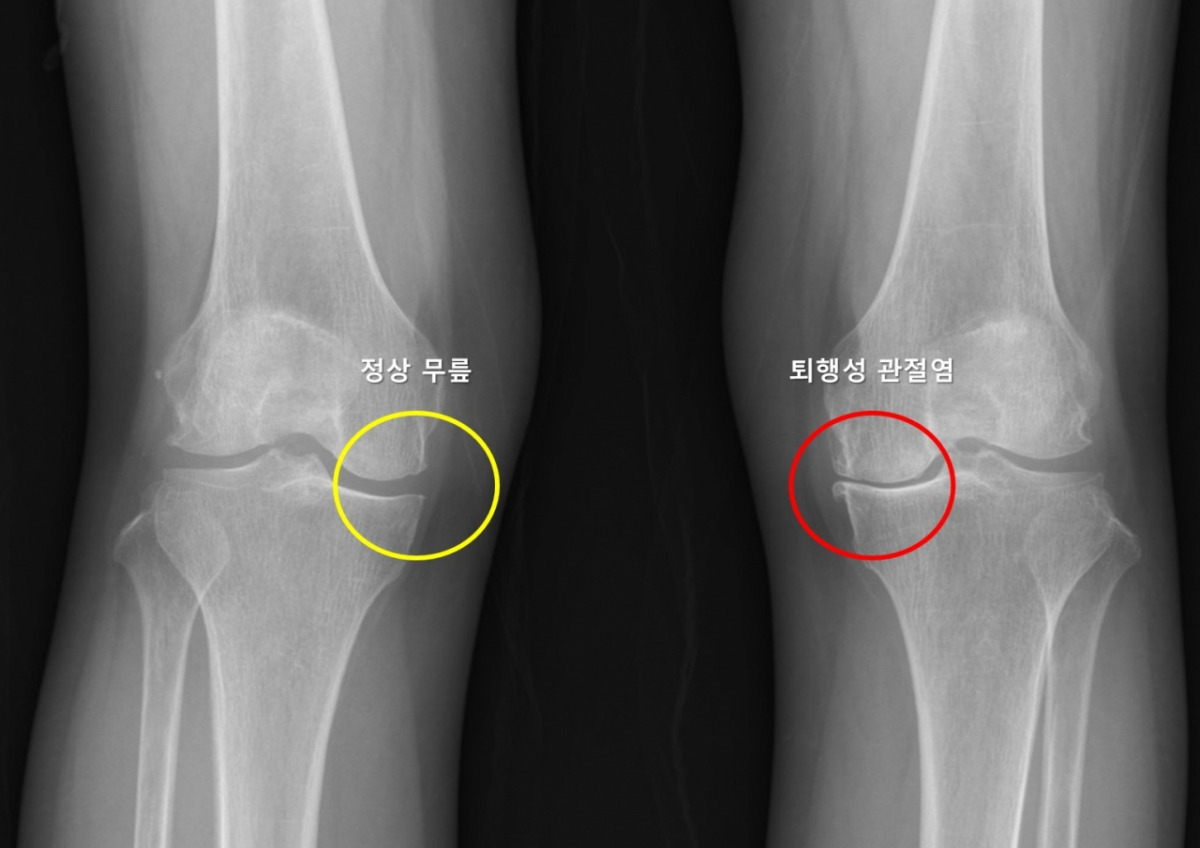

🦵 골관절염 시장, 얼마나 클까?

- 고령 인구 증가 → 환자 수 지속 확대

- 무릎·고관절 중심의 만성 통증 질환

- 안전하고 효과적인 신약 수요 높음

그래서 제약업계에서는 골관절염을 ‘늦게 열리지만 크게 열리는 시장’으로 봅니다.